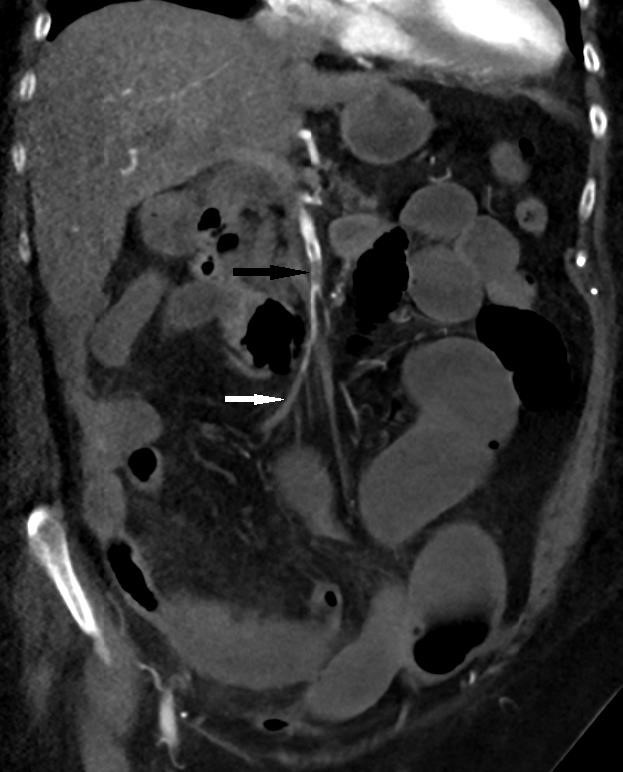

Figure 1: Coronal CT abdomen and pelvis with arterial phase contrast enhancement demonstrating non-occlusive embolus in the proximal SMA (black arrow), becoming occlusive in the distal branches (white arrow). Small bowel dilatation and mesenteric congestion in the right lower abdomen.

A 82-year-old female patient was admitted to the emergency department (ED) with shortness of breath and increasing severe epigastric and central abdominal pain accompanied by vomiting and diarrhea. She was tested positive for SARS -CoV-2 19 by real-time polymerase chain reaction (RT-PCR) in the community. Apart from Bronchial asthma, hypertension, hypothyroidism there were no past medical history of thromboembolic events. On physical examination, the patient was afebrile, had increased respiratory rate (24 breaths per minute) with oxygen saturation of 90% on room air. Her saturation improved to 96% with 2 liters of oxygen, heart rate was at 85 beats per minute and blood pressure was 155/85. There was an epigastric tenderness without guarding or rigidity. Laboratory examination revealed neutrophilic leukocytosis (21,500 /ul white cells with absolute neutrophils 19,700 /ul), normal platelets, elevated C-reactive protein (CRP) at 291 mg/l (standard value: <8 mg/l) and increased creatinine 299 micromol/l with a glomerular filtration rate of 33 ml/min. The liver enzymes and the lipase levels were normal. Following admission, her white cell count (WCC) and CRP continued to rise in which the results were 34,900 /ul and 388 mg/l respectively. However, her blood lactate levels were continued to be less than 2 mmol/l. Her coagulation profile on admission was INR 1.3, PT 13, APTT 43. No acute pathology was detected on Computed Tomography (CT) of the abdomen, which was performed without intravenous contrast (given the global contrast shortage at the time). She was managed with intravenous remdesivir and dexamethasone for her moderate COVID infection. Her abdominal pain was gradually settled in the initial 2 days following admission, however it started to get worsen on the third day of admission with associated worsening shortness of breath and constipation. Examination revealed evidence of severe epigastric and periumbilical tenderness with significant guarding and rigidity. Repeat multiphase CT performed with iodinated contrast demonstrated superior mesenteric artery (SMA) clot, which was nonocclusive proximally, becoming occlusive in the distal branches. Interval development of a long segment of mild small bowel dilatation with a segment of hyperdense mural thickening, mesenteric oedema and a small volume of free fluid raised concern for ischaemic enteritis. There were no features of advanced small bowel ischemia or infarction. Furthermore, CT of the chest revealed evidence of bilateral pulmonary emboli, which were appeared moderate in volume suggested significant coagulopathy. Urgent medical treatment with unfractionated heparin infusion started for anticoagulation. Given her CT abdominal finding on the time of clinical deterioration was not characteristic of bowel wall necrosis and the lactate was remained in the lower levels the surgeons decided to continue close monitoring for the next 24 hours. Unfortunately, she was rapidly deteriorated overnight, and she was taken to the theater on the following day where she underwent a 1.2 meters of small bowel resection. She also underwent a thrombo-embolectomy of the SMA thrombus during the surgery. A relook laparotomy on the following day revealed further ischemic segments and another 70 cm of her bowel was resected. Post operatively she had significant hematemesis and was performed an urgent gastroscopy. This revealed widespread gastric ulceration that unfortunately was not amenable to any endoscopic intervention. Given her significant deterioration, the decision was made to change the direction of care to a comfort base approach. She passed away peacefully following end of life care treatment.